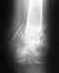

Сегодня при падении у женщины 45 лет пострадало плечо. В связи с выходными в травмпункте удалось только сделать рентген и мягкую перевязку. Большая просьба проконсультировать по прилагаемому снимку (надеюсь там что-то можно разобрать):

1) насколько вероятно то что потребуется операция? 2) хирург сможет осмотреть только в понедельник (травма получена в субботу), при этом нам сказали, что если потребуется операция, то придется ждать минимум две недели. Насколько критично время в данной ситуации? (Может надо срочно ехать в Москву и проситься сделать операцию немедленно).